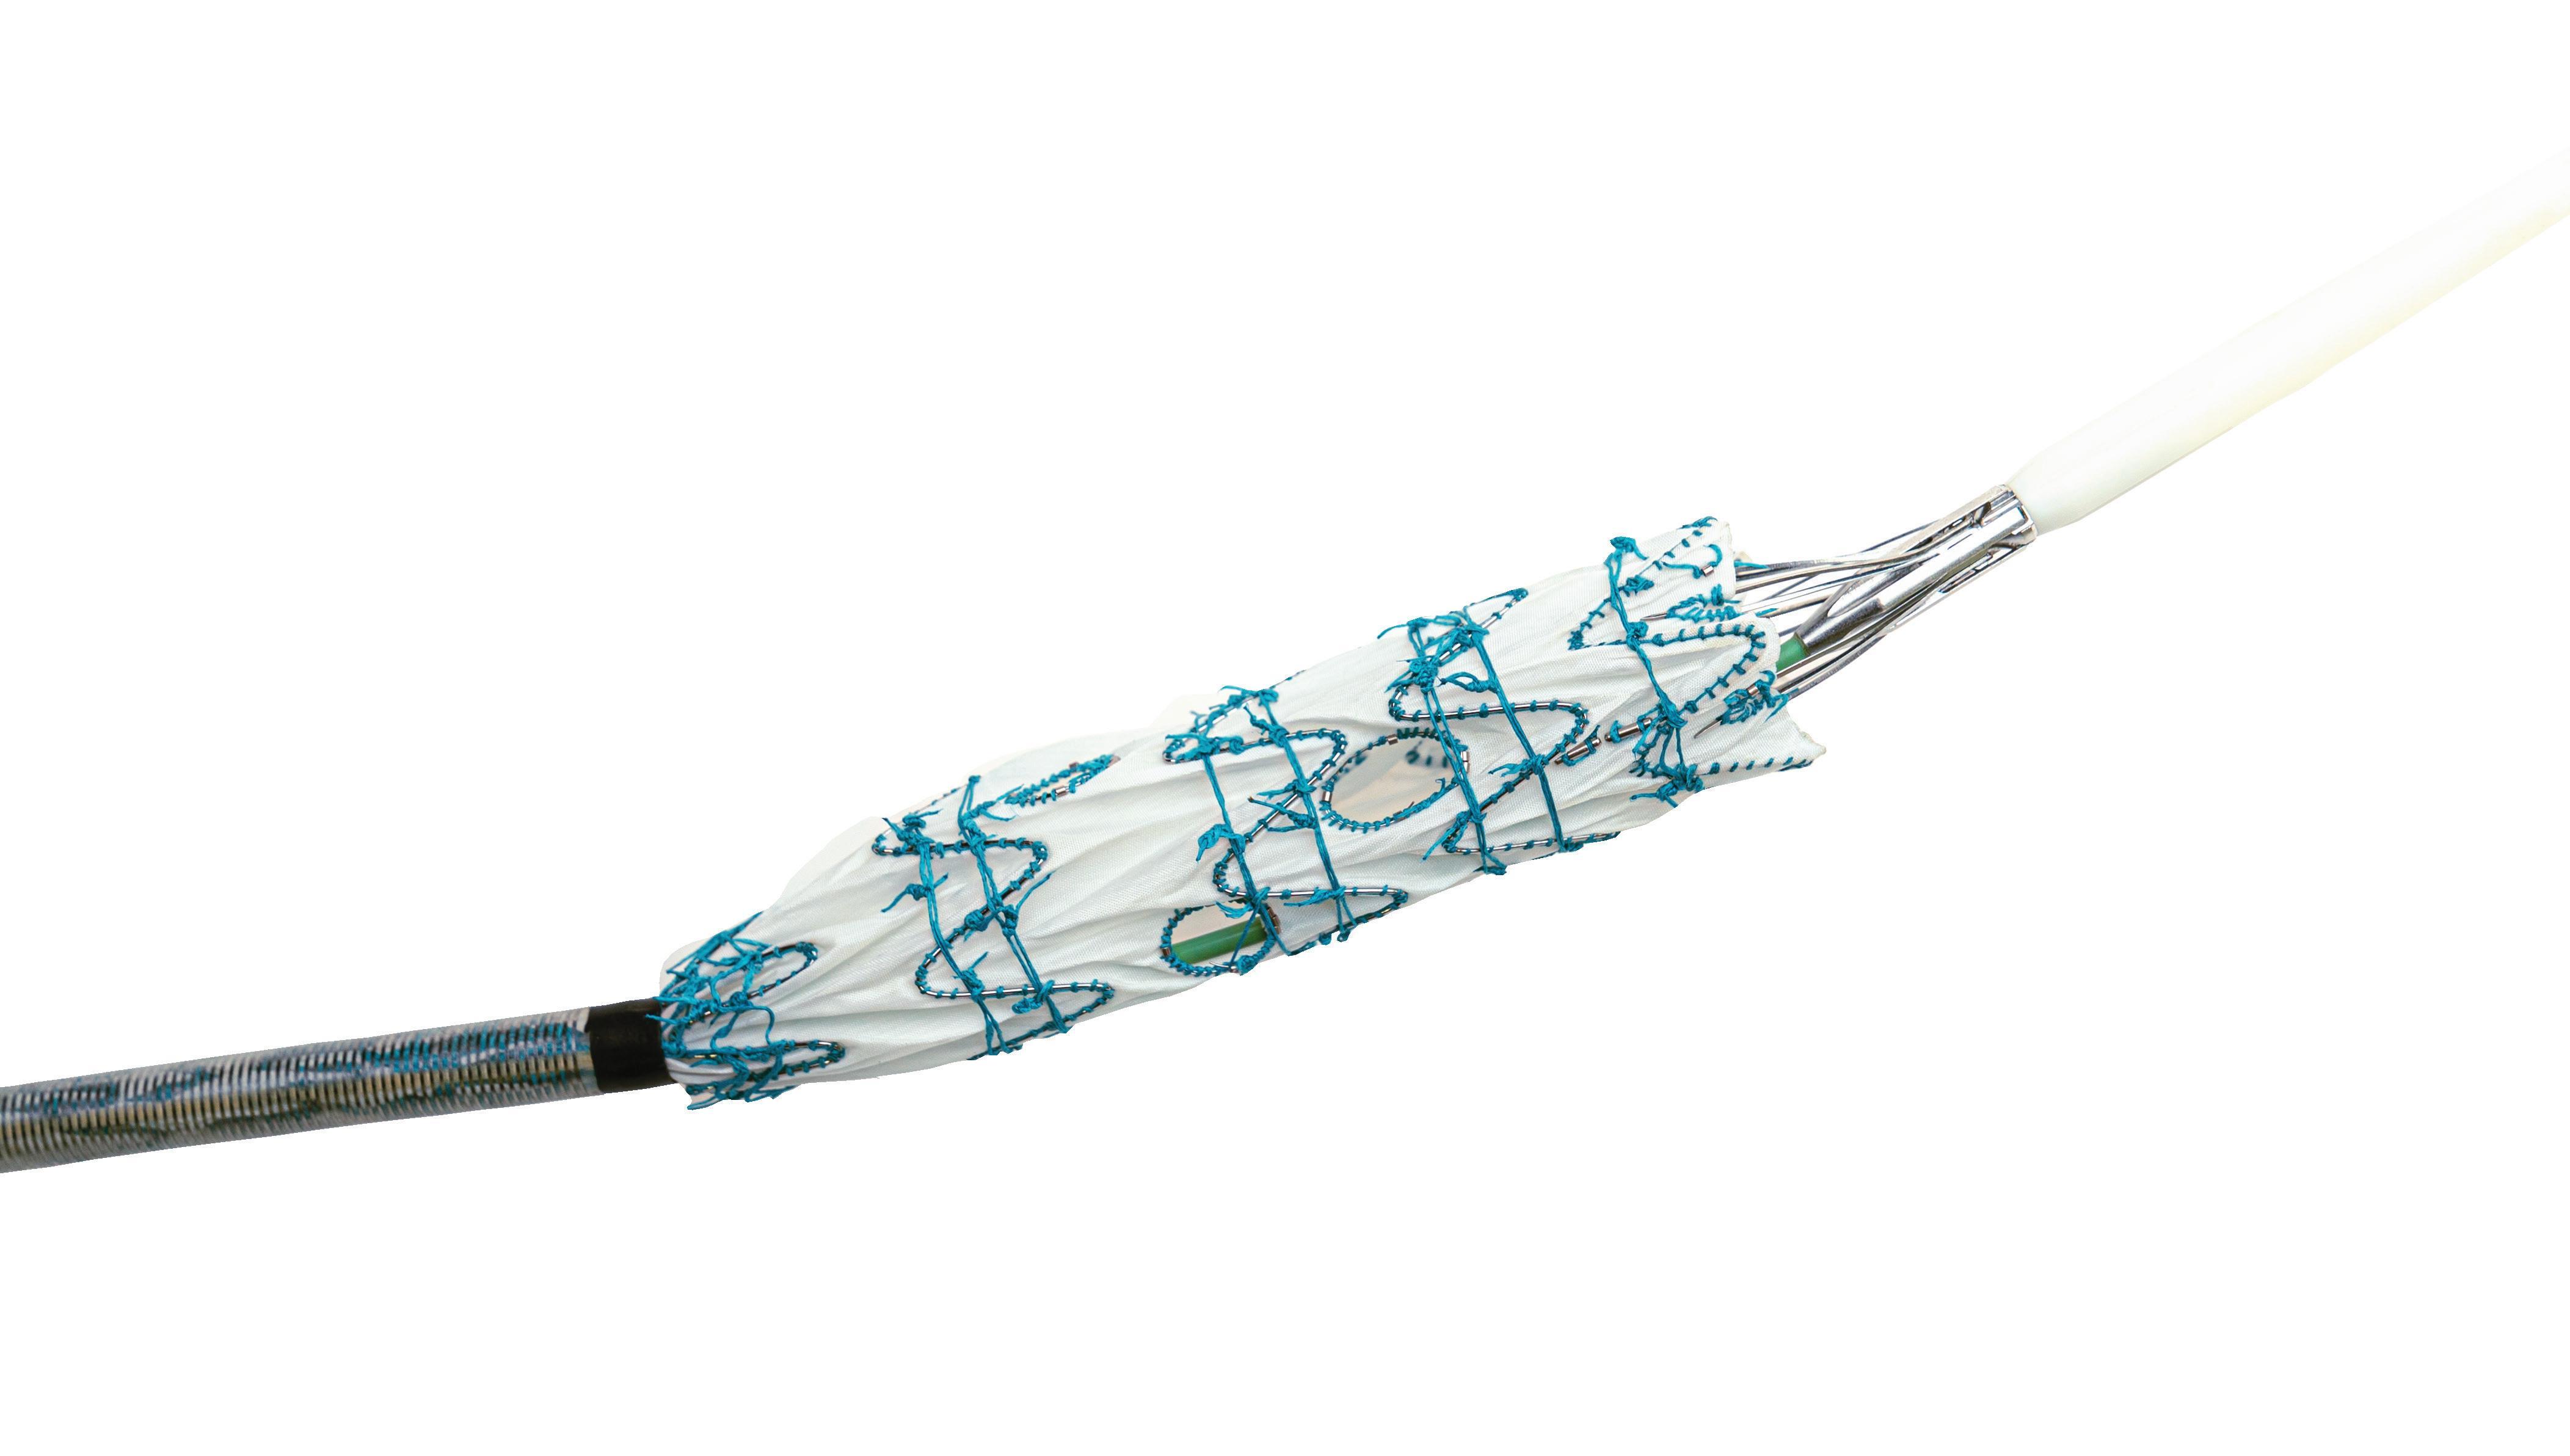

Positive six-month findings from the randomised arteriovenous (AV) fistula arm of Merit Medical’s Wrapsody arteriovenous access efficacy (WAVE) pivotal trial have been revealed. The data were shown at the Cardiovascular and Interventional Radiological Society of Europe (CIRSE) annual congress (14–18 September, Lisbon, Portugal) during a FIRST@ CIRSE presentation. Wrapsody is a cell-impermeable endoprosthesis which is intended to extend long-term vessel patency in dialysis patients.

For more on this story go to page 22.

outcomes of a randomised clinical trial of endothermal ablation versus conventional surgery for great saphenous varicose veins; and a report of Merit Medical’s Wrapsody WAVE trial that demonstrated superior patency versus standard of care in arteriovenous (AV) fistula patients.